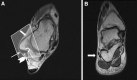

Ankle sonography is one of the most commonly ordered examinations in the field of osteoarticular imaging, and it requires intimate knowledge of the anatomic structures that make up the joint. For practical purposes, the examination can be divided into four compartments, which are analyzed in this pictorial essay: the anterior compartment, which includes the tibialis anterior, extensor hallucis longus, and extensor digitorum longus tendons; the accessory peroneus tertius tendon; and the extensor retinaculum; the medial compartment (tibialis posterior, flexor digitorum longus, and flexor hallucis longus tendons; the flexor retinaculum; the medial collateral-or deltoid-ligament, and the neurovascular bundle); the lateral compartment (peroneus longus, peroneus brevis, and peroneus quartus tendons; superior and inferior peroneal retinacula, lateral collateral ligament); and the posterior compartment (Achilles tendon, plantaris tendon, Kagar's triangle, superficial, and deep retrocalcaneal bursae). Scanning techniques are briefly described to ensure optimal visualization of the various anatomic structures.